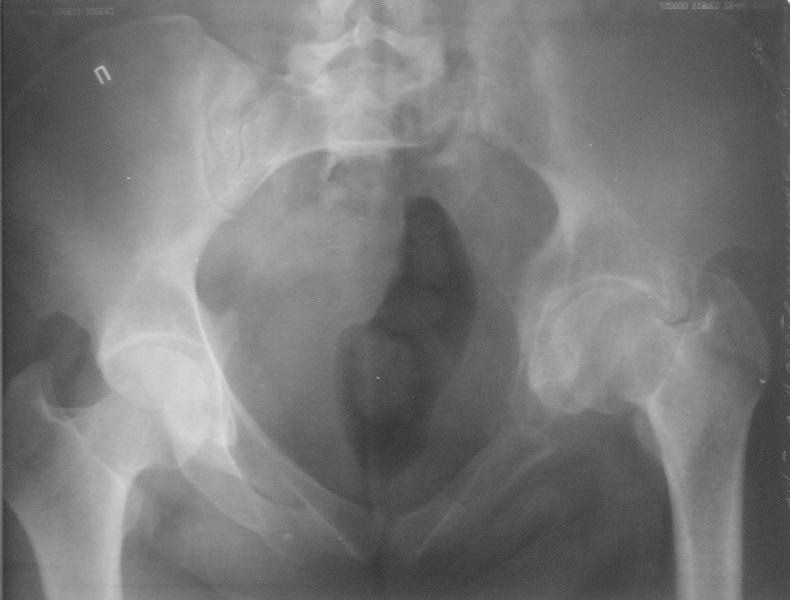

Прооперировали молодую девушку 32 лет спустя 9 мес после травмы.

Имелся стойкий болевой синдром, неопороспособность левой н/конечности, моторные и сенсорные нарушения в левой голени и стопе, патологическая подвижность левой половины таза. Первым этапом закрыто в аппарате исправили деформацию ( в течении 2,5 нед). Вторым закрытое введение илиосакральных винтов в крестец (канюллированные 7,2 мм Chm) + туннелизация зоны псевдоартроза спицама Киршнера, реконструкция передних отделов таза, накостный остеосинтез . Аппарат частично демонтирпован, оставлена "передняя рама" После устранения деформации отмечен регресс неврологической симптоматики, уменьшение болевого синдрома. Интересующие вопросы: 1. Прогноз для сращения псевдоартроза крестца. 2. сроки нагрузки весом левой половины таза. Буду очень признателен за ваши мнения по этому поводу.A female 32 y.o. admitted to our unit 9 months after initial injury with pain, inability to bear weight at the left lower limb, sensor and motor disturbances in the left foot and tibia, with mobility of the left hemipelvis.At first closed reduction was performed by an external fixator within 2,5 weeks. After correction her pain decreased and some neurological progress was achieved. Now two iliosacral screws 7,2 mm were inserted, and anterior lesion was fixed by a plate. External fixator was partially unmounted, only anterior frame left in place.Images attached.How would you evaluate chances of healing of the sacrum with the current position?When would you allow weight-bearing of the left leg?THX in advance.